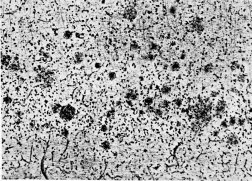

Alois Alzheimer first described the disease in 1907 after he examined the brains of people who had died of a severe dementia. The German psychiatrist noted the presence of abnormal protein deposits, or plaques, piled around nerve cells in the brain and tangled proteins inside the cells. These so-called beta-amyloid plaques and tau tangles have come to be considered the signature of Alzheimer’s disease. Researchers have linked these plaques and tangles, which develop first in the area of the brain used for memory, to the decline in connections between nerve cells and the death of brain cells–changes presumed to be responsible for the brain dysfunctions of the disease.

In the past few years, most scientists studying Alzheimer’s have considered the beta-amyloid plaques to be the crucial factor underlying Alzheimer’s disease. Yet some researchers now suggest that this so-called amyloid hypothesis is overstated and that other entities, including tau tangles, are as important as beta-amyloid.

Beta-amyloid is a tiny protein fragment snipped from a larger protein called amyloid precursor protein. Plaques are a mix of beta-amyloid with remnants of nerve cells and other brain cells.

Tests of nerve cells grown in lab cultures suggest that, in some forms, beta-amyloid itself can be toxic, producing compounds called free radicals that damage nerve cells. Moreover, beta-amyloid plaques are associated with swelling and inflammation, a process that might signal the early stages of nerve cell death.

Blass and like-minded scientists point out that the progressive mental deterioration marking Alzheimer’s disease and the appearance of beta-amyloid plaques don’t necessarily go hand in hand. As many as 20 percent of people diagnosed with Alzheimer’s show no sign of beta-amyloid plaques at autopsy. Likewise, up to 50 percent of people who have relatively high numbers of beta-amyloid plaques in their brains at autopsy showed no sign of mental impairment during their lives.